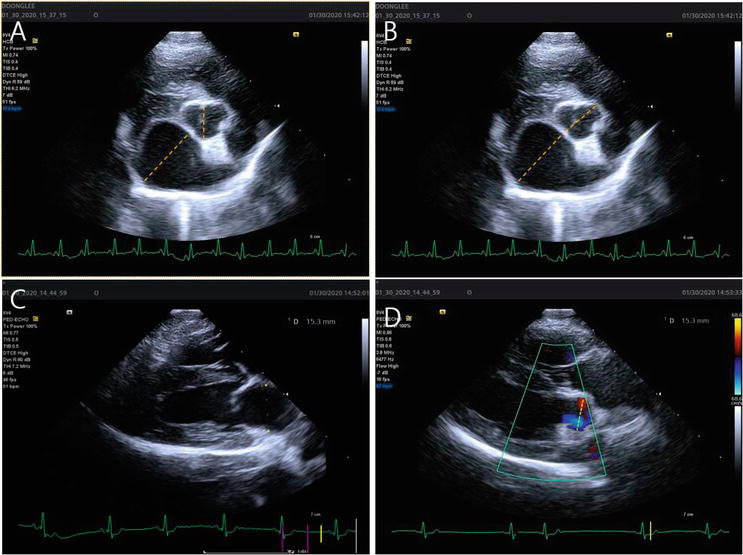

| LA:Ao Ratio | ≥1.6 | Right parasternal short-axis at AV level; early diastole |

Figure 3 - Echocardiographic LA:Ao measurement in right parasternal short-axis view. The method for measurement of left atrial to aortic root ratio (LA/Ao). (A) A LA/Ao obtained from a right parasternal short axis (LA/AoSx) by method 1 (see text). (B) A LA/Ao obtained from a right parasternal short axis (LA/AoSx) by method 2 (see text). (C and D) A LA/Ao obtained from a right parasternal long axis (LA/AoLx). For LA diameter (C), the measurement was made at end-systole 1 to 2 frames before the opening of the mitral valve leaflets. The measurement bisects the atrium extending from the mid-atrial septum in the near field to the bright pericardial echo of the LA lateral wall in the far field and is roughly parallel to the mitral annulus. For Ao diameter (D), the measurement of the aortic valve was made between the opened aortic valve leaflets in an early systolic frame when the Ao diameter is the greatest.

Reference: https://www.intechopen.com/chapters/71522 DOI: 10.5772/intechopen.91819